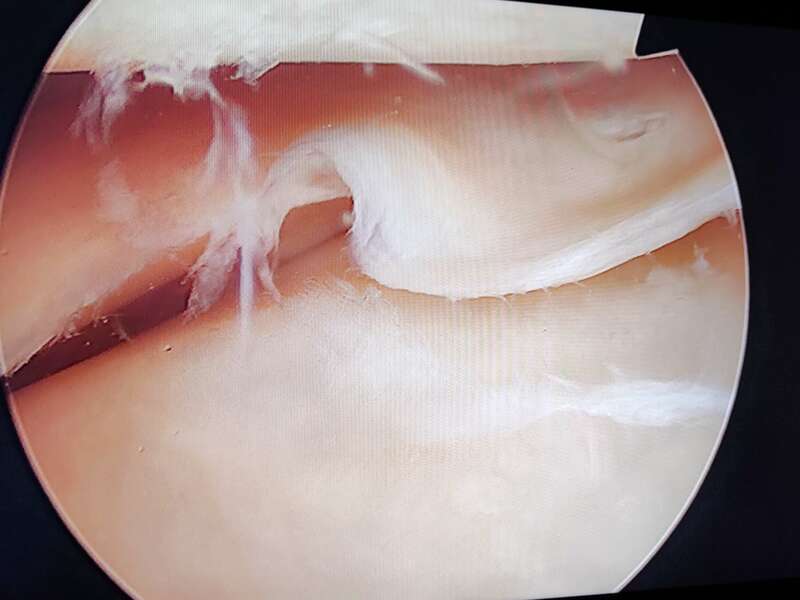

La ménisectomie sous arthroscopie vise à réséquer une lésion méniscale symptomatique tout en conservant un maximum de ménisque sain. L'arthroscopie permet d’explorer l'intérieur du genou, de faire un diagnostic et de traiter des lésions, en particulier méniscales et ligamentaires.

L'Arthroscope est un tube de quelques millimètres de diamètre, muni d'un système optique et d’un système d'éclairage, il est couplé à une caméra vidéo miniaturisée, elle-même reliée à un écran de télévision couleur. Il est mis en place à l'intérieur du genou par un orifice minime, un ou parfois plusieurs autres petits orifices cutanés sont nécessaires pour l'introduction d'instruments fins dans l'articulation. Pendant tout l'examen, le genou est gonflé avec du liquide (sérum physiologique).

L'arthroscopie permet de regarder : la cavité articulaire, les ménisques (interne et externe), le cartilage (de la rotule, du fémur, du tibia), la membrane synoviale (poche qui entoure l’articulation), et les ligaments croisés. Elle permet de réaliser une cartographie lésionnelle de votre genou.

De grandes avancées technologiques ont vu le jour ces-dernières années. L'utilisation d’instruments miniaturisés de haute précision permet désormais d’effectuer des méniscectomies « a minima » pour conserver un maximum de ménisque sain.

Album photo